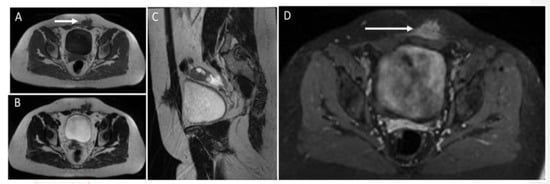

Figure 18. MR study of an endometriotic nodule (arrows) in the left rectus abdominis muscles and subcutaneous tissue. Endometriotic implants inside muscle are well characterized on MR. They show heterogeneously low signal on T1 (A) and T2 images (images B,C) and strong enhancement after the injection of contrast agent (D). Sagittal reconstruction (C) shows the extension of the endometriotic nodule into fat tissue, fascia, and intramuscular location.